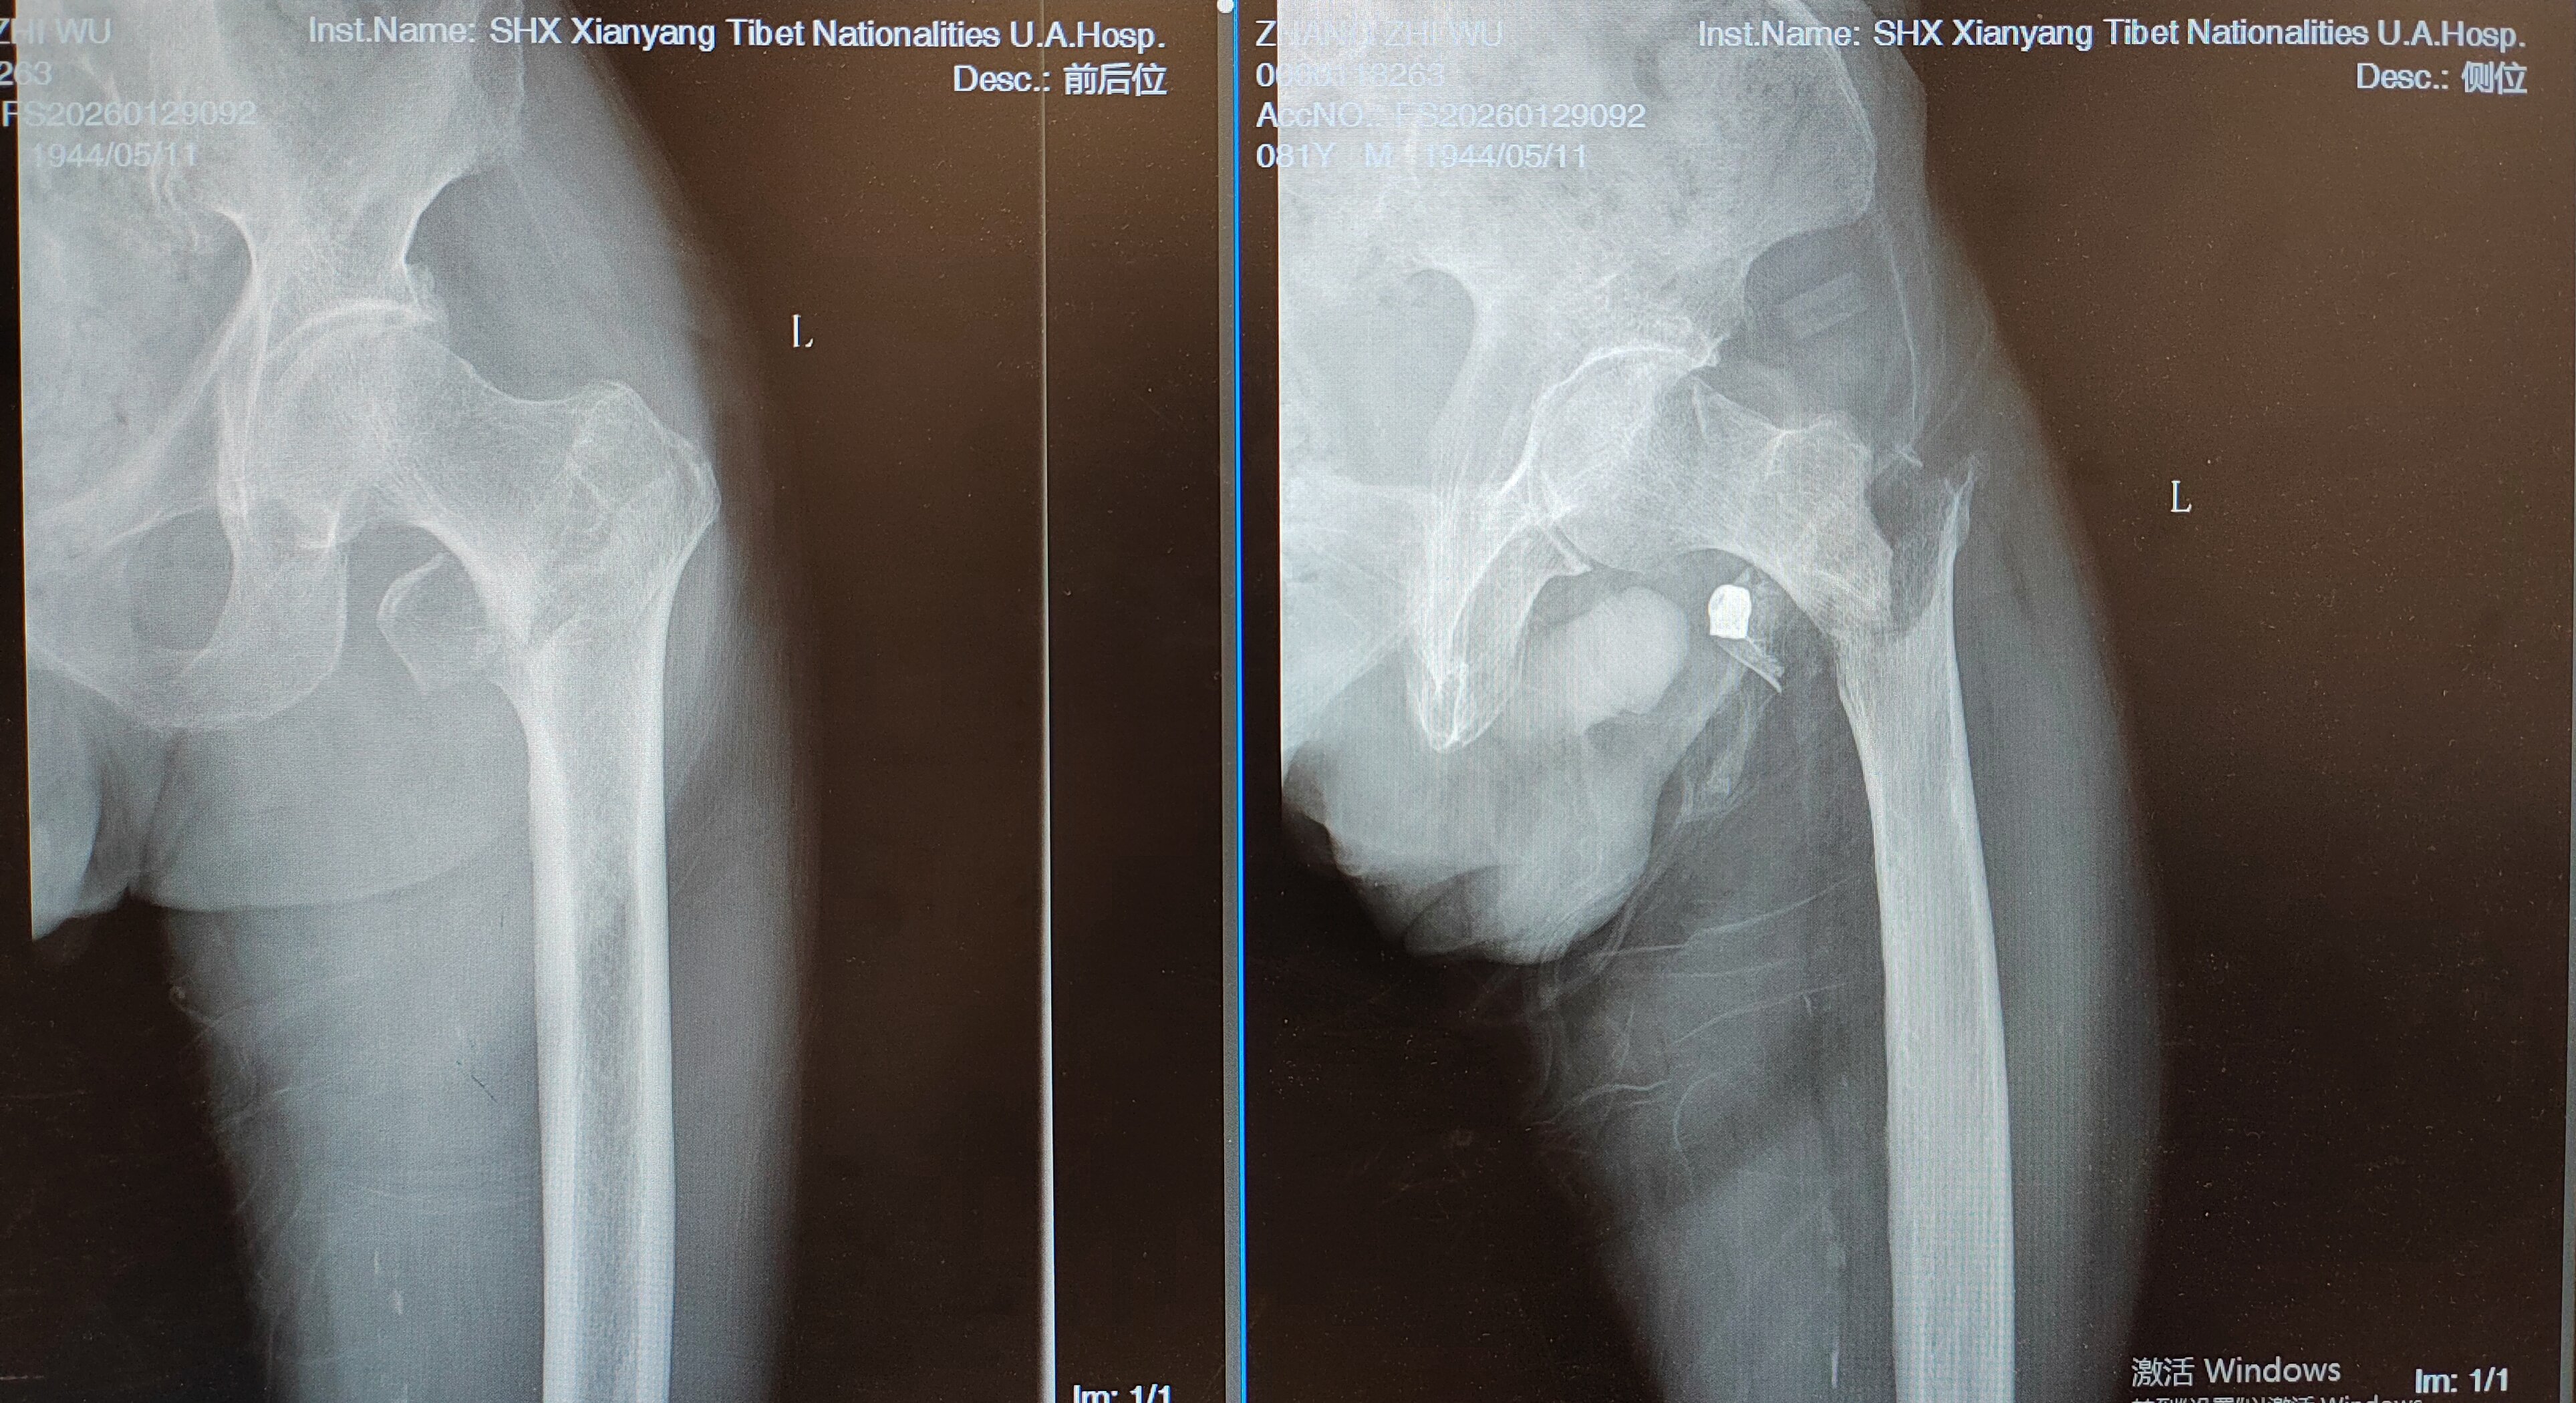

2026年1月底,81岁的张爷爷行走时不慎摔倒,致左髋部肿痛、活动受限,被紧急送往附属医院骨科就诊。经影像学检查,患者被确诊为左侧股骨转子间粉碎性骨折。具有挑战性的是,患者既往病史极为复杂:20年高血压病、2型糖尿病、腔隙性脑梗死病史,2个半月前刚因急性心肌梗死行心脏冠脉支架植入术,基础病多、身体耐受差,手术与麻醉风险极高。

(患者术前X光片)

患者入院后,骨科赵昕副主任医师第一时间接诊,查体发现患者左下肢呈外旋、短缩畸形(较健侧短缩约 3cm),左髋部肿胀压痛,结合影像学结果与复杂既往病史,全面评估病情及风险。为确保治疗安全,骨科主任马群莹主任医师牵头,联合赵昕副主任医师及团队医生启动多学科协作(MDT)诊疗模式,召集神经心血管内科、呼吸内分泌科、泌尿外科等科室专家联合会诊,针对患者基础病制定精准调控方案,为手术创造安全条件。